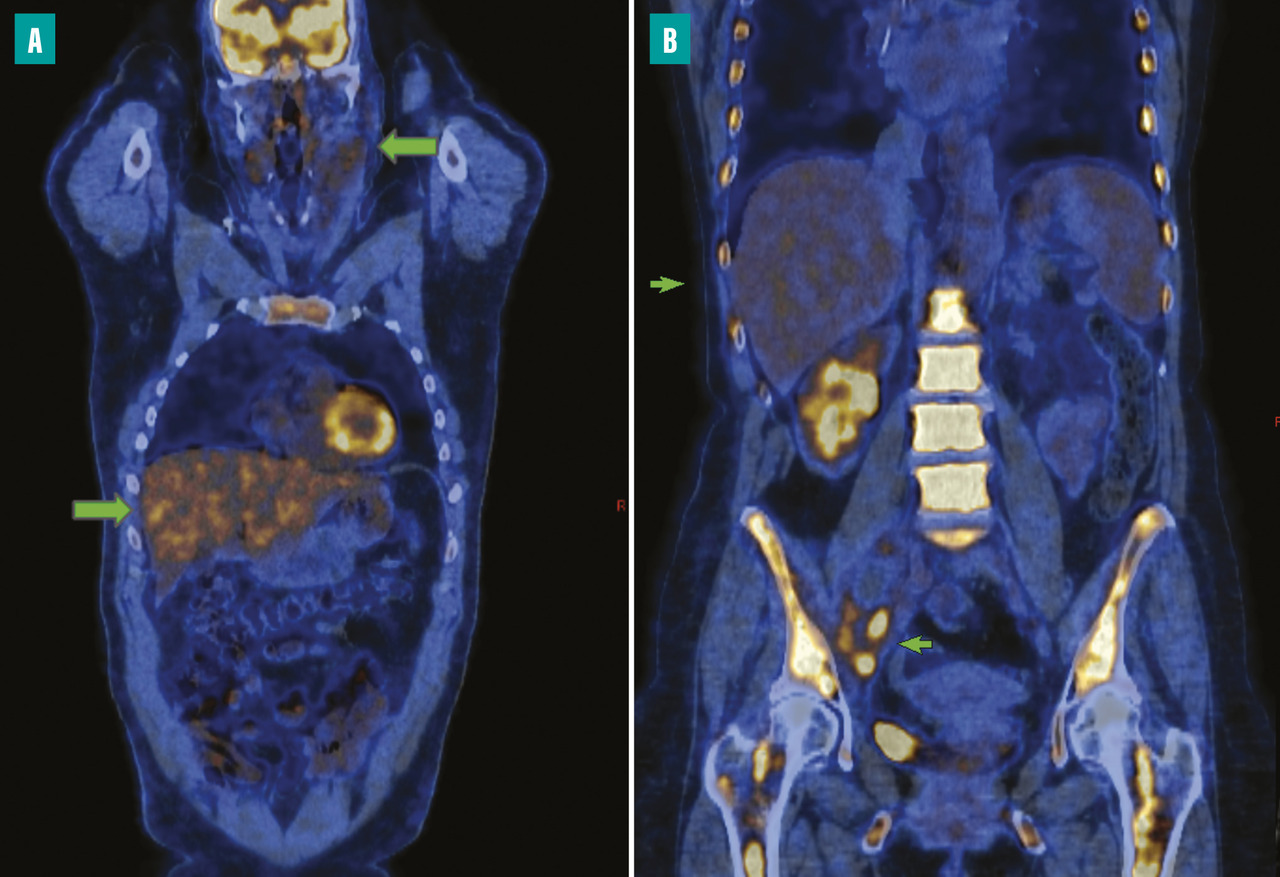

Intérêt du volume métabolique tumoral total

La TEP de référence permet le calcul de la masse tumorale appelée volume métabolique tumoral total (TMTV), qui est un facteur pronostique de survie dans les lymphomes de Hodgkin localisés et avancés. Ce facteur est d’autant plus intéressant qu’il est cumulatif avec la réponse métabolique après deux cycles, permettant d’isoler trois groupes pronostiques : très favorable (faible TMTV et réponse complète), très défavorable (TMTV élevé et réponse incomplète) et intermédiaire (avec un des deux facteurs).

L’étude ancillaire du protocole H10 portant sur ces paramètres a ainsi montré la définition de nouveaux groupes pronostiques avec une survie sans progression à cinq ans allant de 95 % pour le groupe pronostique le plus favorable à 25 % pour le groupe le plus défavorable sur cette population de lymphome de Hodgkin localisé.9

Si des règles de standardisation de la mesure sont encore attendues, la détermination du TMTV en tant que facteur décisionnel fait déjà l’objet d’un essai clinique international prospectif décisionnel évaluant la possibilité d’omission de la radiothérapie chez les patients présentant un lymphome de Hodgkin localisé, ayant un faible TMTV initial et une réponse complète à deux cycles (essai RAFTING-NCT04866654).